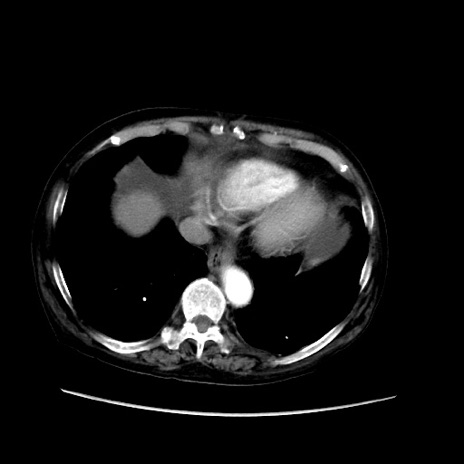

症例31(横断像)

【症例】80歳代 女性

【主訴】腹部膨満感

【現病歴】他院にて肝硬変にてフォロー中。1週間前から便秘、腹部膨満感、臍部腫瘤あり受診となる。

【既往歴】肝硬変

【身体所見】腹部膨隆あり、皮膚変化なし、疼痛なし。

【データ】WBC 4600、CRP 0.25